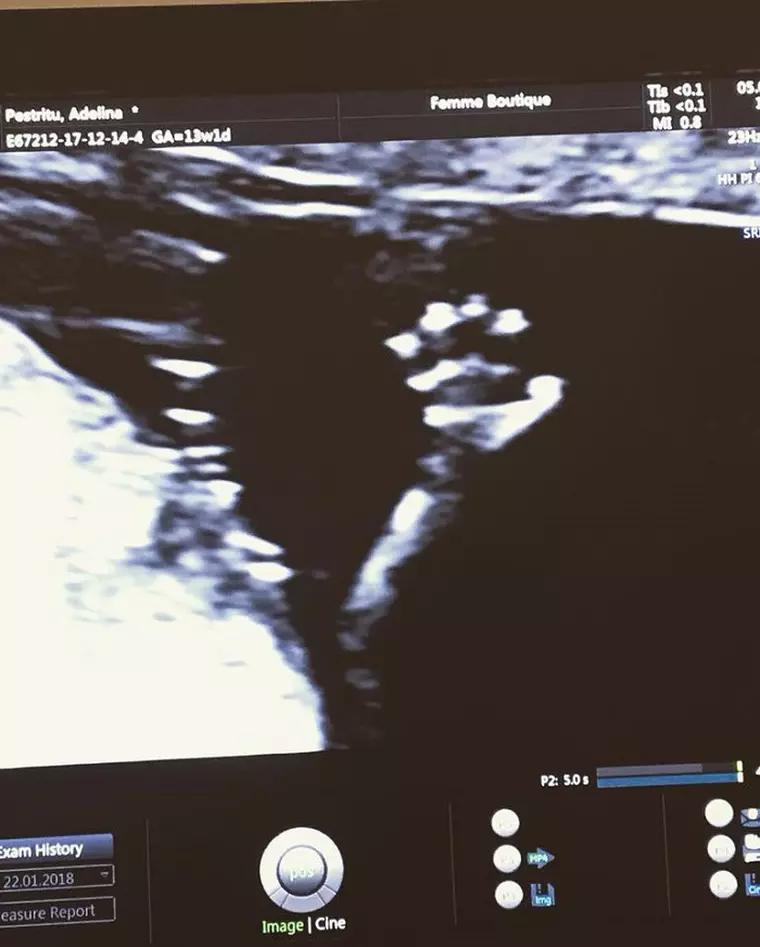

Se pare că Adelina Pestriţu va deveni mamă de fetiţă. Sarcina decurge perfect. Vedeta a arătat şi prima imagine cu micuţa, la 18 săptămâni.

„Intr-o zi dedicata femeilor si mai ales celor care sunt si mamici, am ales sa impartasim cu voi minunata veste ca bebelusul pe care il asteptam este o fetita ![]()

Micuta este foarte cuminte si totul decurge perfect! Asteptam cu nerabdare sa o strangem in brate.

P.S. Si pentru ca m-a rugat sa va salut, am atasat si o fotografie cu ea, chiar daca are numai 18 saptamani